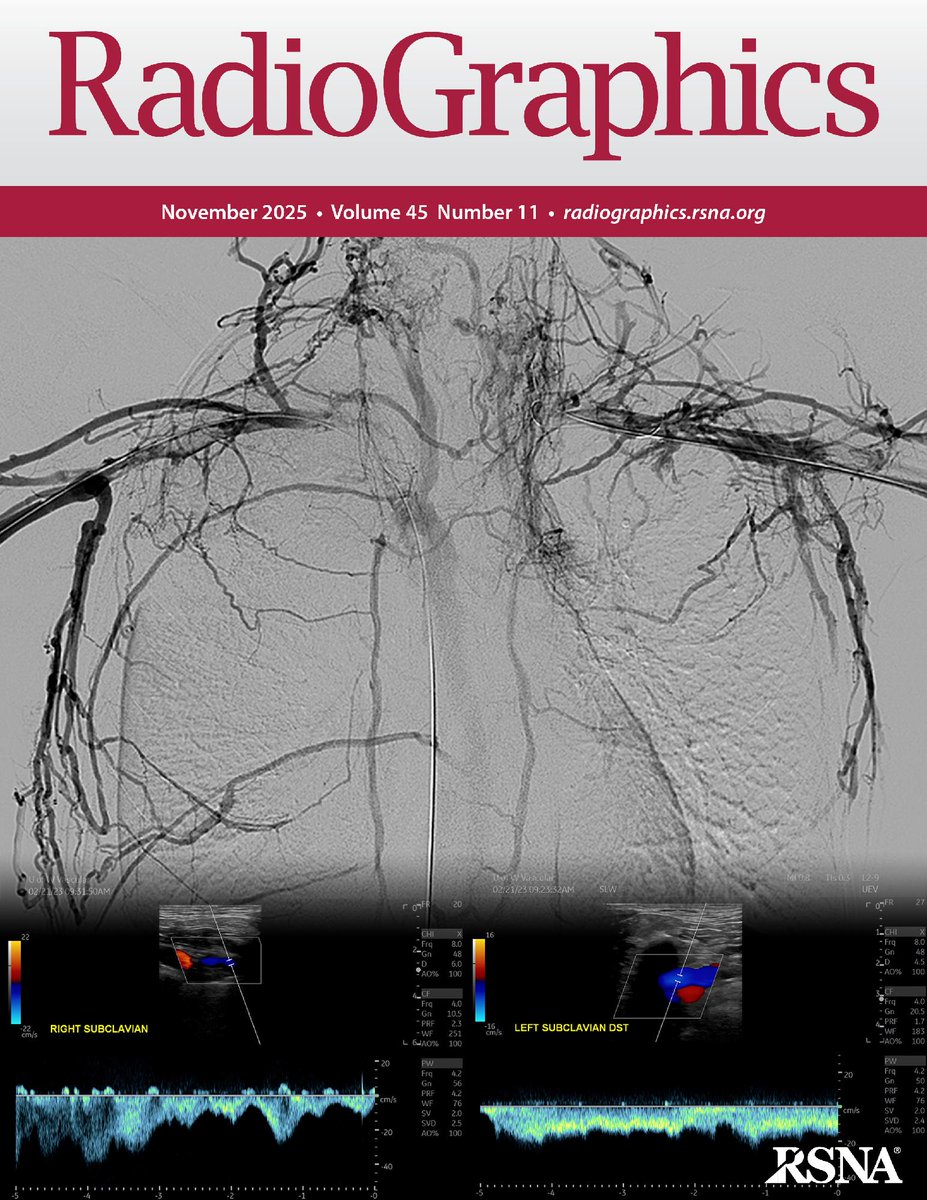

Thoracic central vein obstruction is increasingly device-related. Endovascular recanalization and stent reconstruction enable rapid symptom relief and durable patency when guided by meticulous imaging, planning, and technique. https://t.co/PPhBTAHdUF